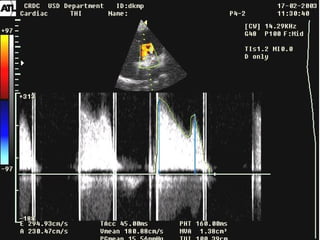

Echocardiography:Echocardiography:

Dilatation LA and RV;

Stenosis of mitral valve orifice

– the rate transmitral

patological flow

Echocardiography:Echocardiography: Dilatation LA andRV; Stenosis of mitral valve orifice – the rate transmitral patological flow